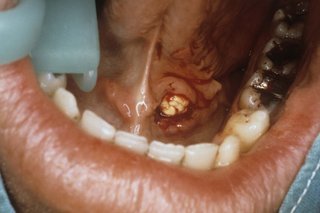

The inside of a person's mouth showing their lower teeth and bottom lip. There is something large and white (a salivary gland stone) under their tongue.

Salivary gland stones are white and hard.